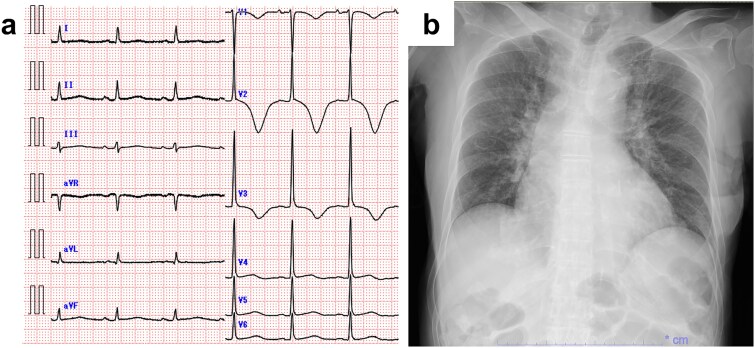

感染性心内膜炎(IE)是一种危及生命的疾病,通常需要手术干预;然而,在手术禁忌的情况下,保守治疗依赖于适当的抗生素治疗。此外,抗生素的修改可能是关键,因为某些药物在解决感染和相关并发症方面可能更优越。我们提出的情况下,一个88岁的妇女与IE由于血管链球菌,成功地治疗口服抗生素。经胸超声心动图显示二尖瓣和主动脉瓣赘生物,伴有中度至重度瓣膜功能障碍。尽管静脉注射氨苄西林6周,她的病情改善有限。策略性地改用左氧氟沙星导致了显著的临床进展,显著减少了植被大小和正常的炎症标志物。左氧氟沙星的有效性,由于其生物膜渗透和杀菌活性,表明定制抗生素方案有可能取得积极的结果。这个病例说明,即使标准治疗不成功,仔细的抗生素调整也会显著影响治疗过程。

Infective endocarditis (IE) is a life-threatening condition, often requiring surgical intervention; however, in cases where surgery is contraindicated, conservative management relies on appropriate antibiotic therapy. Moreover, modification of antibiotics can be critical, as certain agents may be superior in resolving infection and associated complications. We present the case of an 88-year-old woman with IE due to Streptococcus anginosus, successfully treated with oral antibiotics. Transthoracic echocardiography revealed vegetations on the mitral and aortic valves, along with moderate-to-severe valvular dysfunction. Despite 6-week treatment with intravenous ampicillin, her condition showed limited improvement. A strategic switch to levofloxacin led to remarkable clinical progress, with significantly reduced vegetation size and normalized inflammatory markers. The effectiveness of levofloxacin, due to its biofilm penetration and bactericidal activity, indicates the potential for customized antibiotic regimens to achieve positive outcomes. This case illustrates that even when standard treatment is unsuccessful, careful antibiotic adjustment can significantly impact the therapeutic course.